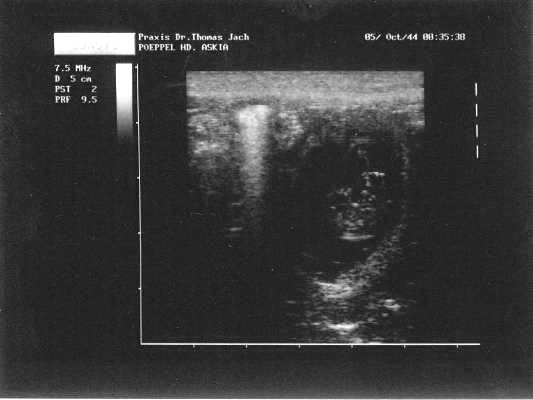

60. Tag:

Askia hat ihr Frühstück heute gar nicht gefressen. Überhaupt nimmt sie nur

noch Leckerlies, welche nicht aus ihrem gewohnten Futter bestehen und diese

nimmt sie auch nur mit Überredungskünsten an. Sie würde sich zu gern oben in

unser Bett legen aber wir möchten, dass sie unten bleibt damit wir sie

besser im Auge haben. Allgemein ist Askia aber noch ziemlich ruhig. Wir

haben den Eindruck, dass sich Askias Babybauch ein Stück nach unten

verlagert hat und werden sie weiterhin beobachten.

59.

Tag:

Heute Morgen hat Askia ihr Frühstück nur zur Hälfte gefressen. Laut

Trächtigkeitskalender ist dieses Verhalten ganz normal, da der freie Platz

in Askias Bauch immer kleiner wird. Wir bieten ihr nun kleinere Portionen

an. - Nachdem wir gestern eine von Askias Decken in die Wurfkiste gelegt

haben, hat sich Askia zum ersten Mal von alleine in die Kiste gelegt.

Ansonsten gibt es aber keine weiteren Veränderungen.